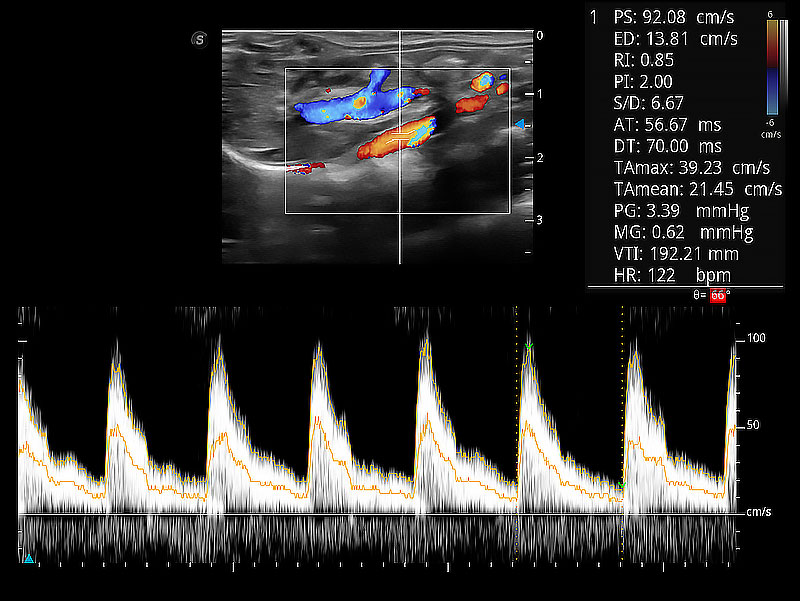

極大提升超低速微細(xì)血流的檢出能力,同時(shí)更精準(zhǔn)地濾除軟組織和超聲信號(hào),為獸用醫(yī)生提供以往無(wú)法通過(guò)常規(guī)血流獲得的疾病診斷信息。

隨著取樣門位置改變,頻譜多普勒包絡(luò)可進(jìn)行自動(dòng)眼蹤測(cè)量,且可自由配置測(cè)量的參數(shù)。